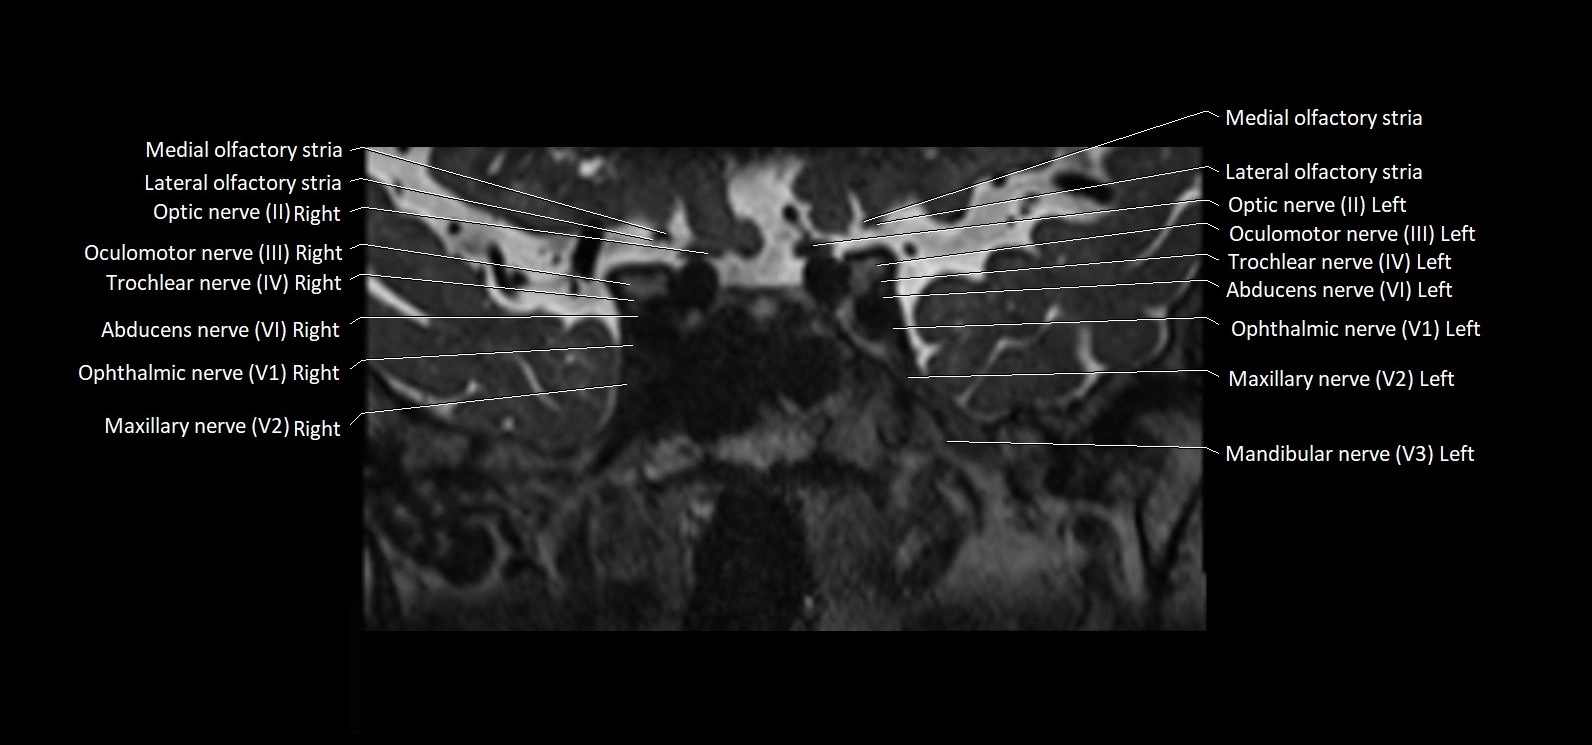

• The abducens nerve is a small, thin, linear structure

• Best visualized on high-resolution T2-weighted 3D MRI sequences (e.g., FIESTA or CISS)

• Seen as a hypointense (dark) line running from the brainstem at the pontomedullary junction, traversing the prepontine cistern, and entering Dorello’s canal under the petrosphenoidal ligament, then into the cavernous sinus, and finally the orbit

• May be challenging to visualize in standard MRI due to its small size

• Pathology may be inferred by absence, displacement, or enhancement of the nerve